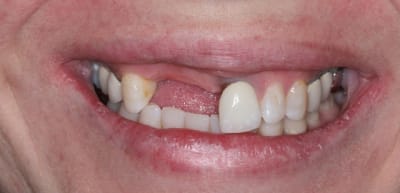

Bon ben j'ai implanté avant d'avoir refait la 21. Du coup j'ai mésialé la pose de 11 pour compenser la distalisation de 21.

Au final je n'ai pas fait de greffe osseuse... et j'ai réalisé une technique de rouleau sur 11-12 mais je reste un peu court à mon goût.

J'ai mis en place des transitoires sur 11-12-21 pour temporiser 3 mois pour voir la maturation des tissus mous.

Je réaliserai dans un second temps des piliers procera.

Je mets quelques photos de la patiente au cab et du prothèsiste d'Epinal.

La vraie difficulté a été de retrouver le milieu incisif pour déterminer la position des implants.